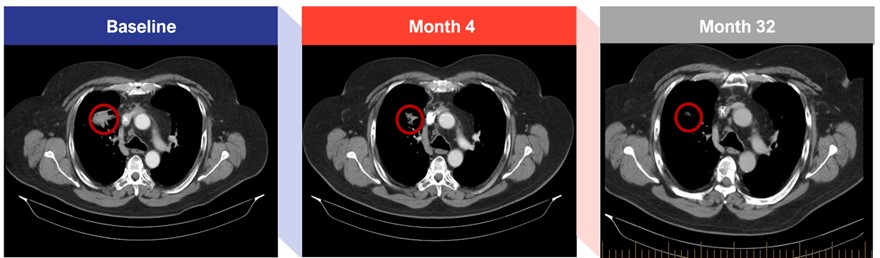

● |

The CR was observed in a patient with advanced SCLC who was previously treated with the carboplatin/etoposide and atezolizumab (a PD-L1 blocker) regimen in the first line followed by a treatment with nivolumab (a PD-1 blocker) in the second line. After progression on prior regimens this patient joined the trial and had a PR at week 17 which was confirmed at week 25. This patient was dosed with CTX-471 for more than three years with a durable PR, and in Q4 2023, following tumor regression observed by CT-Scan, the patient was tested by PET scan and a CR was determined. Below is a series of CT scan images from this patient of the largest mass (RUL Lung) which was ~4 cm at baseline. |